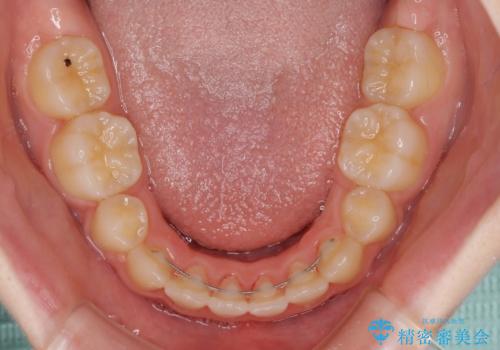

乳歯が残っている 目立たない装置での抜歯矯正

- 八重歯と乳歯が残っていることを気にして来院された患者様です。

乳歯が3歯残っており、下顎は左右ともに後続永久歯がない状態でした。

口元が突出しており、口が閉じにくかったため、乳歯を含め上下5歯を抜歯して矯正治療を行うこととしました。

下顎の乳歯は永久歯と比べて幅が大きいため、抜歯した場合のスペースが大きく、治療には長期間を要することが一般的です。

今回の患者様は中学生ということもあり、成人の患者様と比べ動きが速く、2年間で治療を終えることができました。